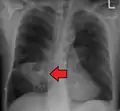

Lung abscesses are often on one side and single involving posterior segments of the upper lobes and the apical segments of the lower lobes as these areas are gravity dependent when lying down. Presence of air-fluid levels implies rupture into the bronchial tree or rarely growth of gas forming organism.